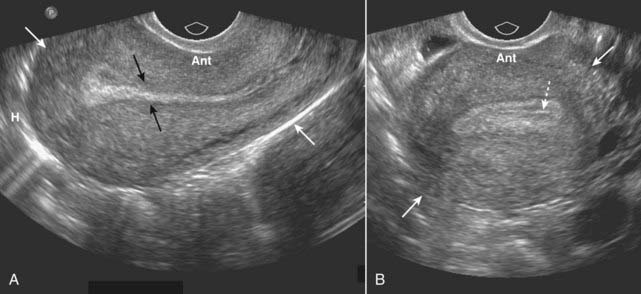

image

Figure 19-22 Pelvic inflammatory disease, sagittal and transverse views, US.

A, A fluid-filled and dilated fallopian tube (FT) containing pus and debris (solid black arrow) representing a pyosalpinx is demonstrated. B, Due to progressive inflammation, there is fusion of a dilated and tortuous fallopian tube (solid black arrow, FT) and the adjacent ovary (solid white arrow, OV) producing a tubo-ovarian complex.